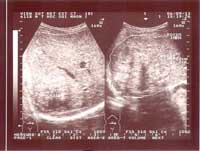

Một số hình ảnh siêu âm tổn thương gan do sán lá gan lớn:

Hình ảnh 1: Khối tổn thương gan do SLGL điển hình, Khối lớn với micro ap xe bên trong | Hình ảnh 2: Khối tổn thương gan do SLG điển hình: Khối lớn và có nhiều micro áp - xe bên trong |